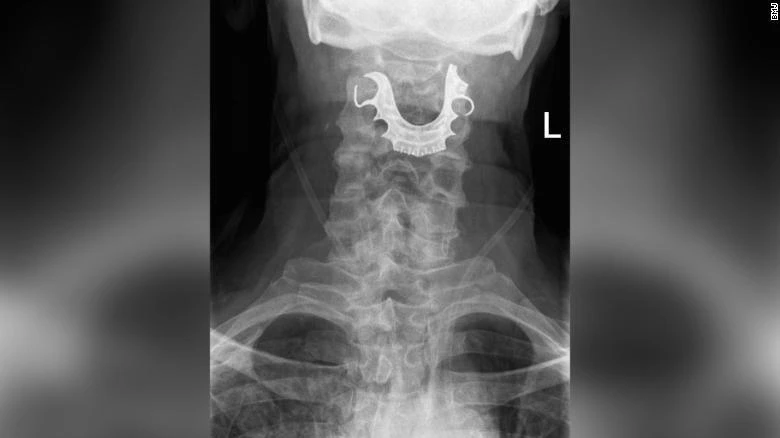

Cuối cùng, liệu trình chẩn đoán đã xác định được một vật thể hình bán nguyệt nằm chặn ngang dây thanh quản của ông, gây ra các vết xước và sưng tấy trong vòm họng. Người đàn ông đã được đưa vào phẫu thuật khẩn cấp để gỡ bỏ hàm răng giả. Ông đã phải ở lại bệnh viện trong sáu ngày sau đó.